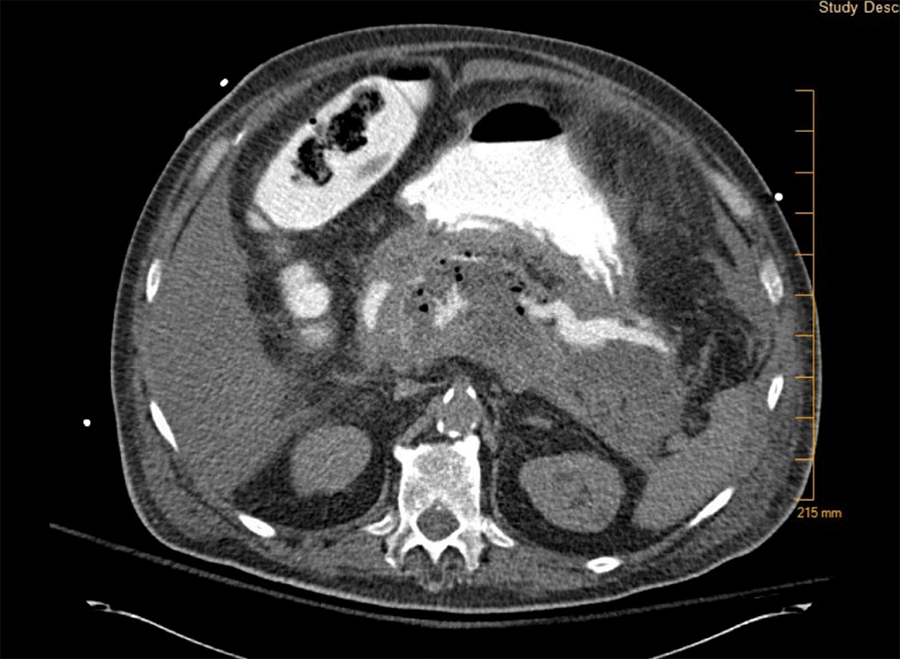

Computed tomography (CT) abdomen and pelvis without contrast performed about four hours after arrival to the ED showed extensive pancreatic parenchymal necrosis. An initial scan was unable to localize the fistula, which was thought to be from the duodenum versus the splenic flexure colon (Figure 1).

Figure 1. CT Abdomen Pelvis Showing Extensive Pancreatic Parenchymal Necrosis With Loculated Fluid Collection Measuring 18.8 × 7.8 × 7.2 cm. Published With Permission